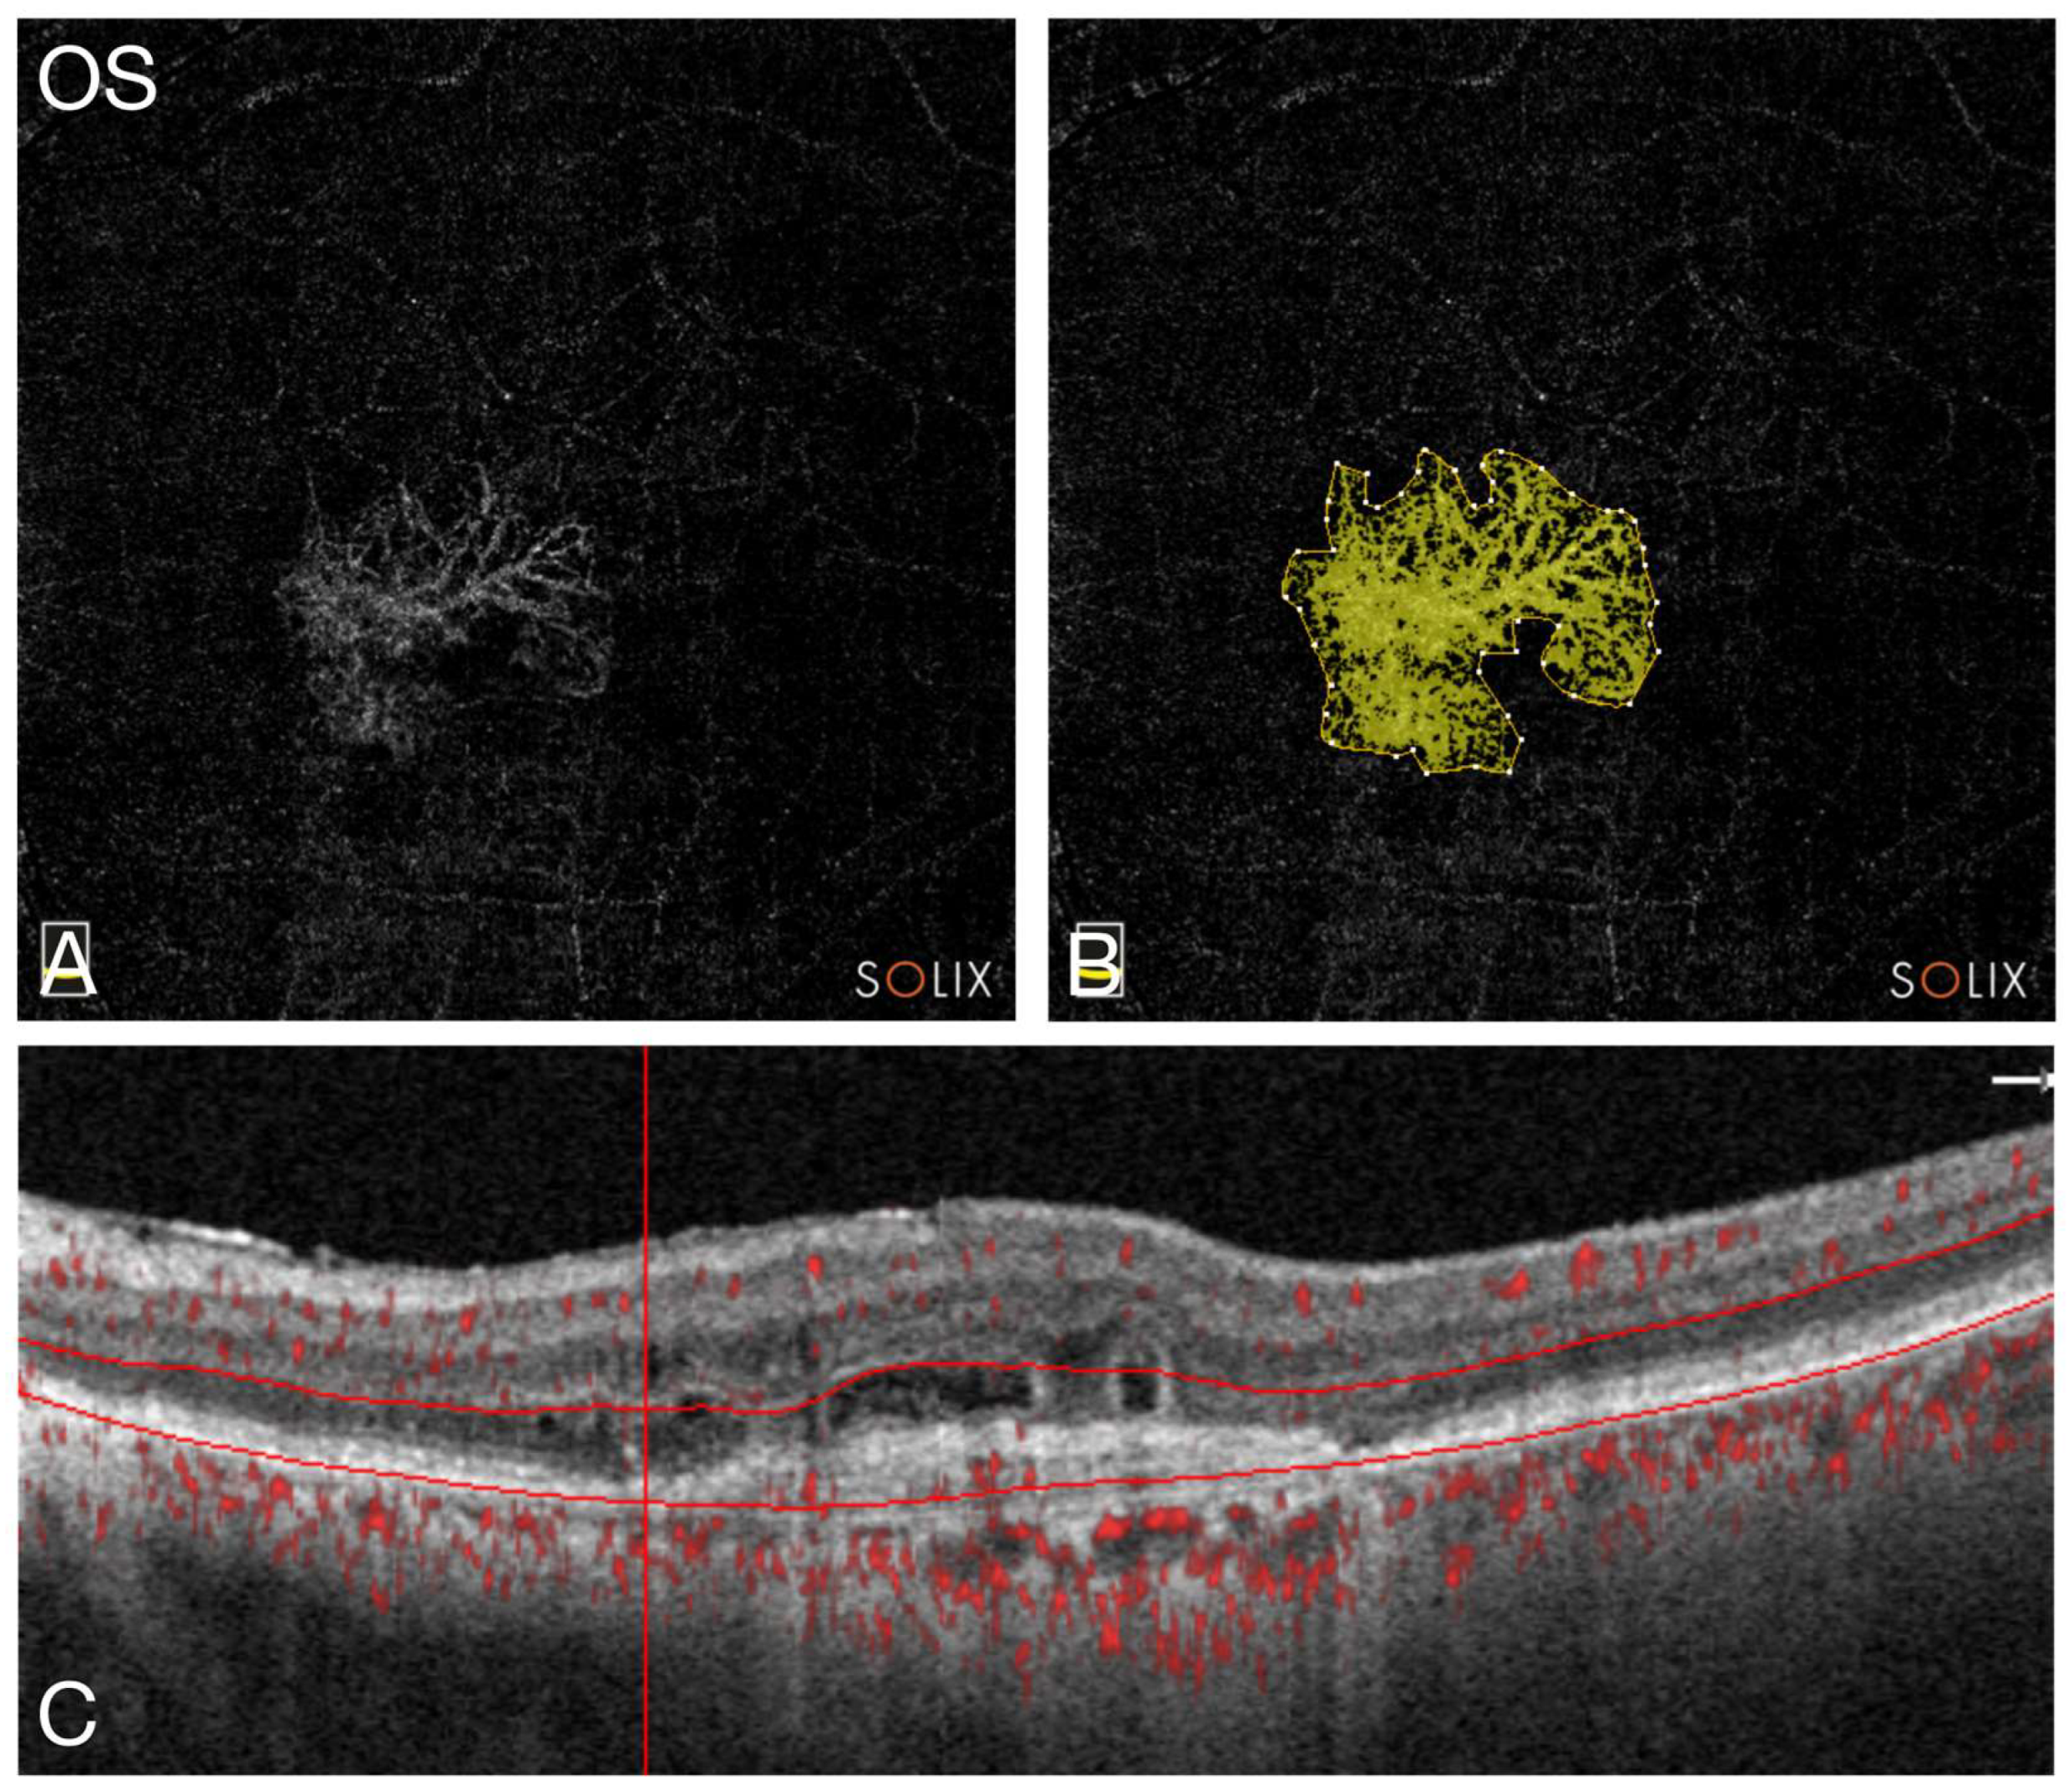

2.4. Image Analysis